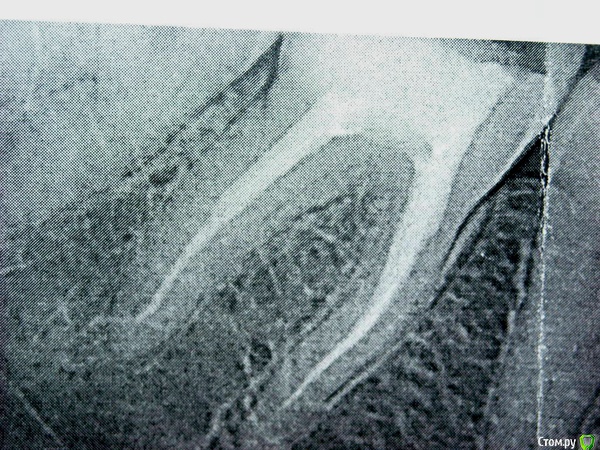

maya1515 Опубликовано 26 октября, 2015 Автор Поделиться Опубликовано 26 октября, 2015 (изменено) Здравствуйте. Еще раз ) Очень и очень нужна помощь. Меня терзают подозрения. Итак, вот снимок - хирург сказал, что облом "не очень глубоко" и можно сделать "вкладку" и коронку. Вытащил обломок и поставил временную пломбу покая я подумаю.Но внешняя стенка зуба тоже, кажется, треснута (как я вижу глазом непрофессионала, не знаю, может просто сколотая какая-то). И внизу есть тоненькая темная полосочка (а если это кариес?) Ну и вот, по факту, от зуба осталась только эта внешняя стенка, сегодня хирург ее сточил даже немного.. Но болей совершенно нет и не было в этом зубе. (Нерв удален давно еще).Сколько ни читаю - советуют не связываться и если скол ниже десны - лучше удалять. Но хирург заверил, что люди даже с более глубоким сколом сохраняют зуб.Денег нет вообще сейчас. Спросила про мет-керамику - 10 000 (назвали наверное саму коронку без остального ). Сумма может возрасти до 3-4 раз, мне кажется. Не понимаю, что же делать. Времени - неделя или две от силы , пока временная пломба стоит. Рискнуть на коронку или удалять? Я так понимаю, на визите к ортопеду скорее всего предложат делать)(Снимок ДО удаления осколка.) Изменено 26 октября, 2015 пользователем maya1515 Ссылка на комментарий

red_butler Опубликовано 26 октября, 2015 Поделиться Опубликовано 26 октября, 2015 По этим снимкам не видно уровня перелома. Но если протезирование возможно, как вариант вкладка и временная коронка. Это позволит выиграть время для решения финансовых вопросов. Ссылка на комментарий